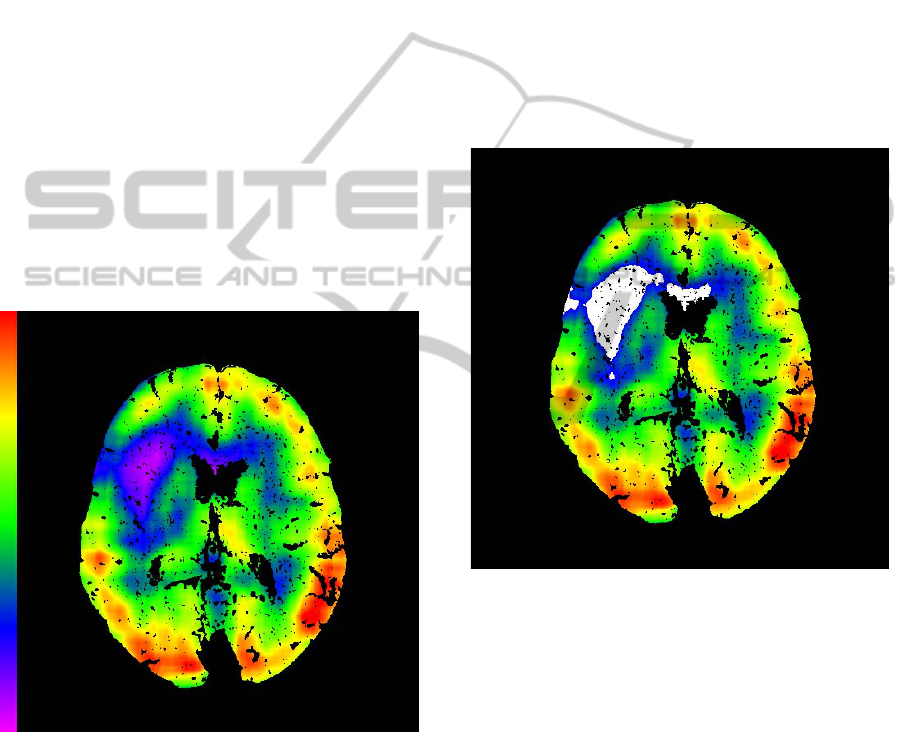

Subtraction follows after the denoising process

(Figure 1). It is based on voxel by voxel basis.